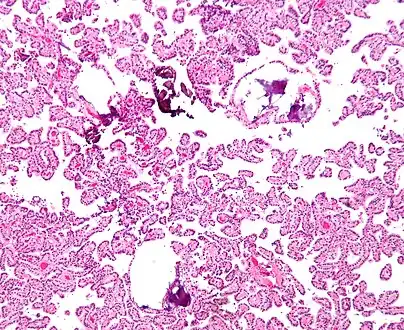

Micrograph of a choroid plexus papilloma. H&E stain.

Plexuspapillom Detail

Plexuspapillom Overview